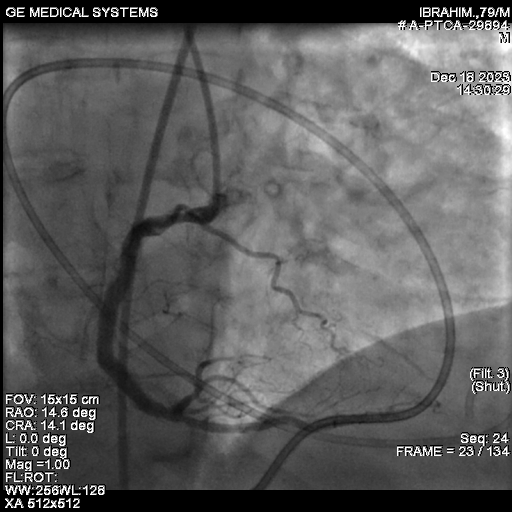

After adequate lesion preparation, we deployed a 4x 38 mm DES. The post-PCI angiogram confirmed a successful final result in the RCA.Following the successful procedure, the patient was shifted to the CCU. Unfortunately, he rapidly developed hypotension and sweating. An urgent ECHO was performed, which revealed a massive pericardial effusion (PE).We maintained continuous pericardial aspiration. The patient's ACT was 280, and Protamine was administered to reverse the heparin effect. A check angiogram ruled out any wire-induced perforation, suggesting the perforation was likely iatrogenic from the temporary pacing wire that had been placed for Rotapro support. Pericardial aspiration continued, and CTS opinion was sought, with the high risk of surgical intervention being explained to the family.At this critical juncture, given the refractory nature of the bleeding, we looked to a new strategy. Literature supports the use of intra-pericardial thrombin injection as a bailout strategy for iatrogenic pericardial tamponade. The response to the intra-pericardial thrombin injection was prompt. The patient's hemodynamics gradually improved. He had an uncomplicated recovery and was discharged five days later.